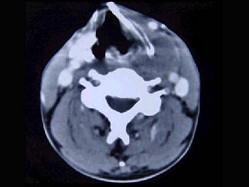

问题 男性,40岁,发现左侧颈部小包块,CT、MRI检查如图所示,请选择最可能的诊断 ( )

选项 A、肿大淋巴结 B、副神经节瘤 C、神经纤维瘤 D、海绵状血管瘤 E、神经鞘瘤

答案 D